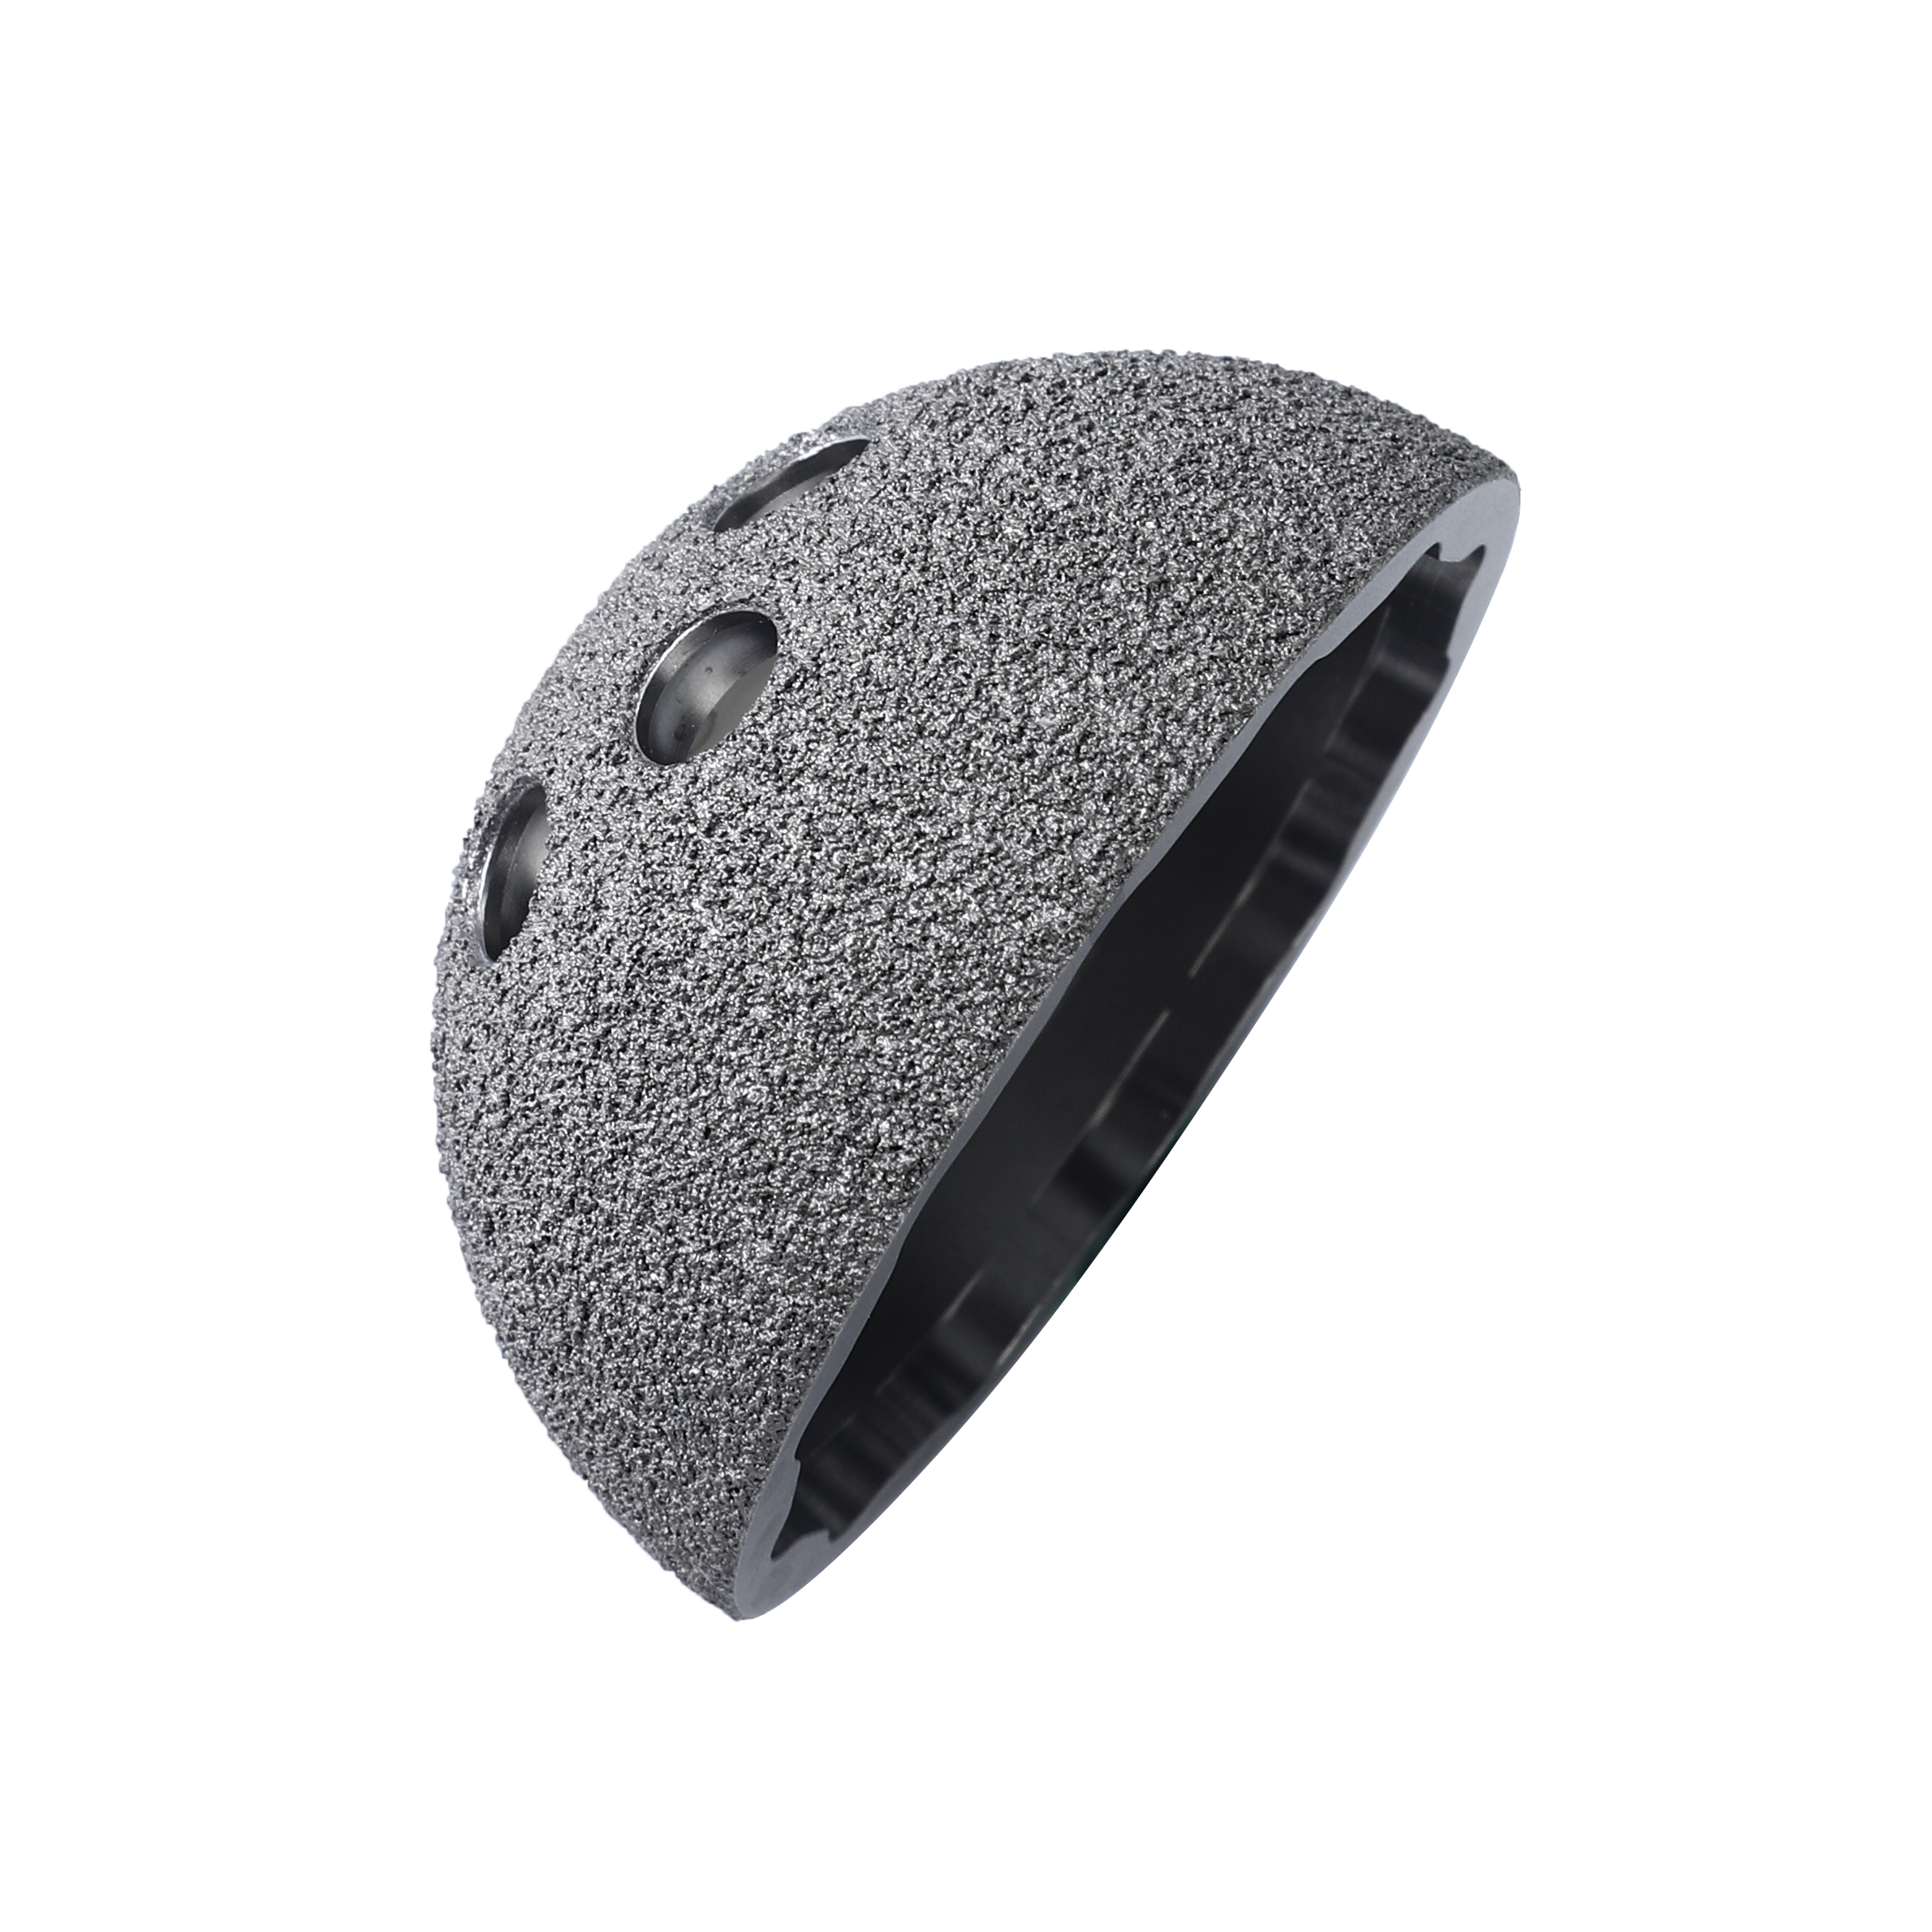

BC Acetabular Cup

Cementless. As part of the STANDFIRM Hip Replacement System.